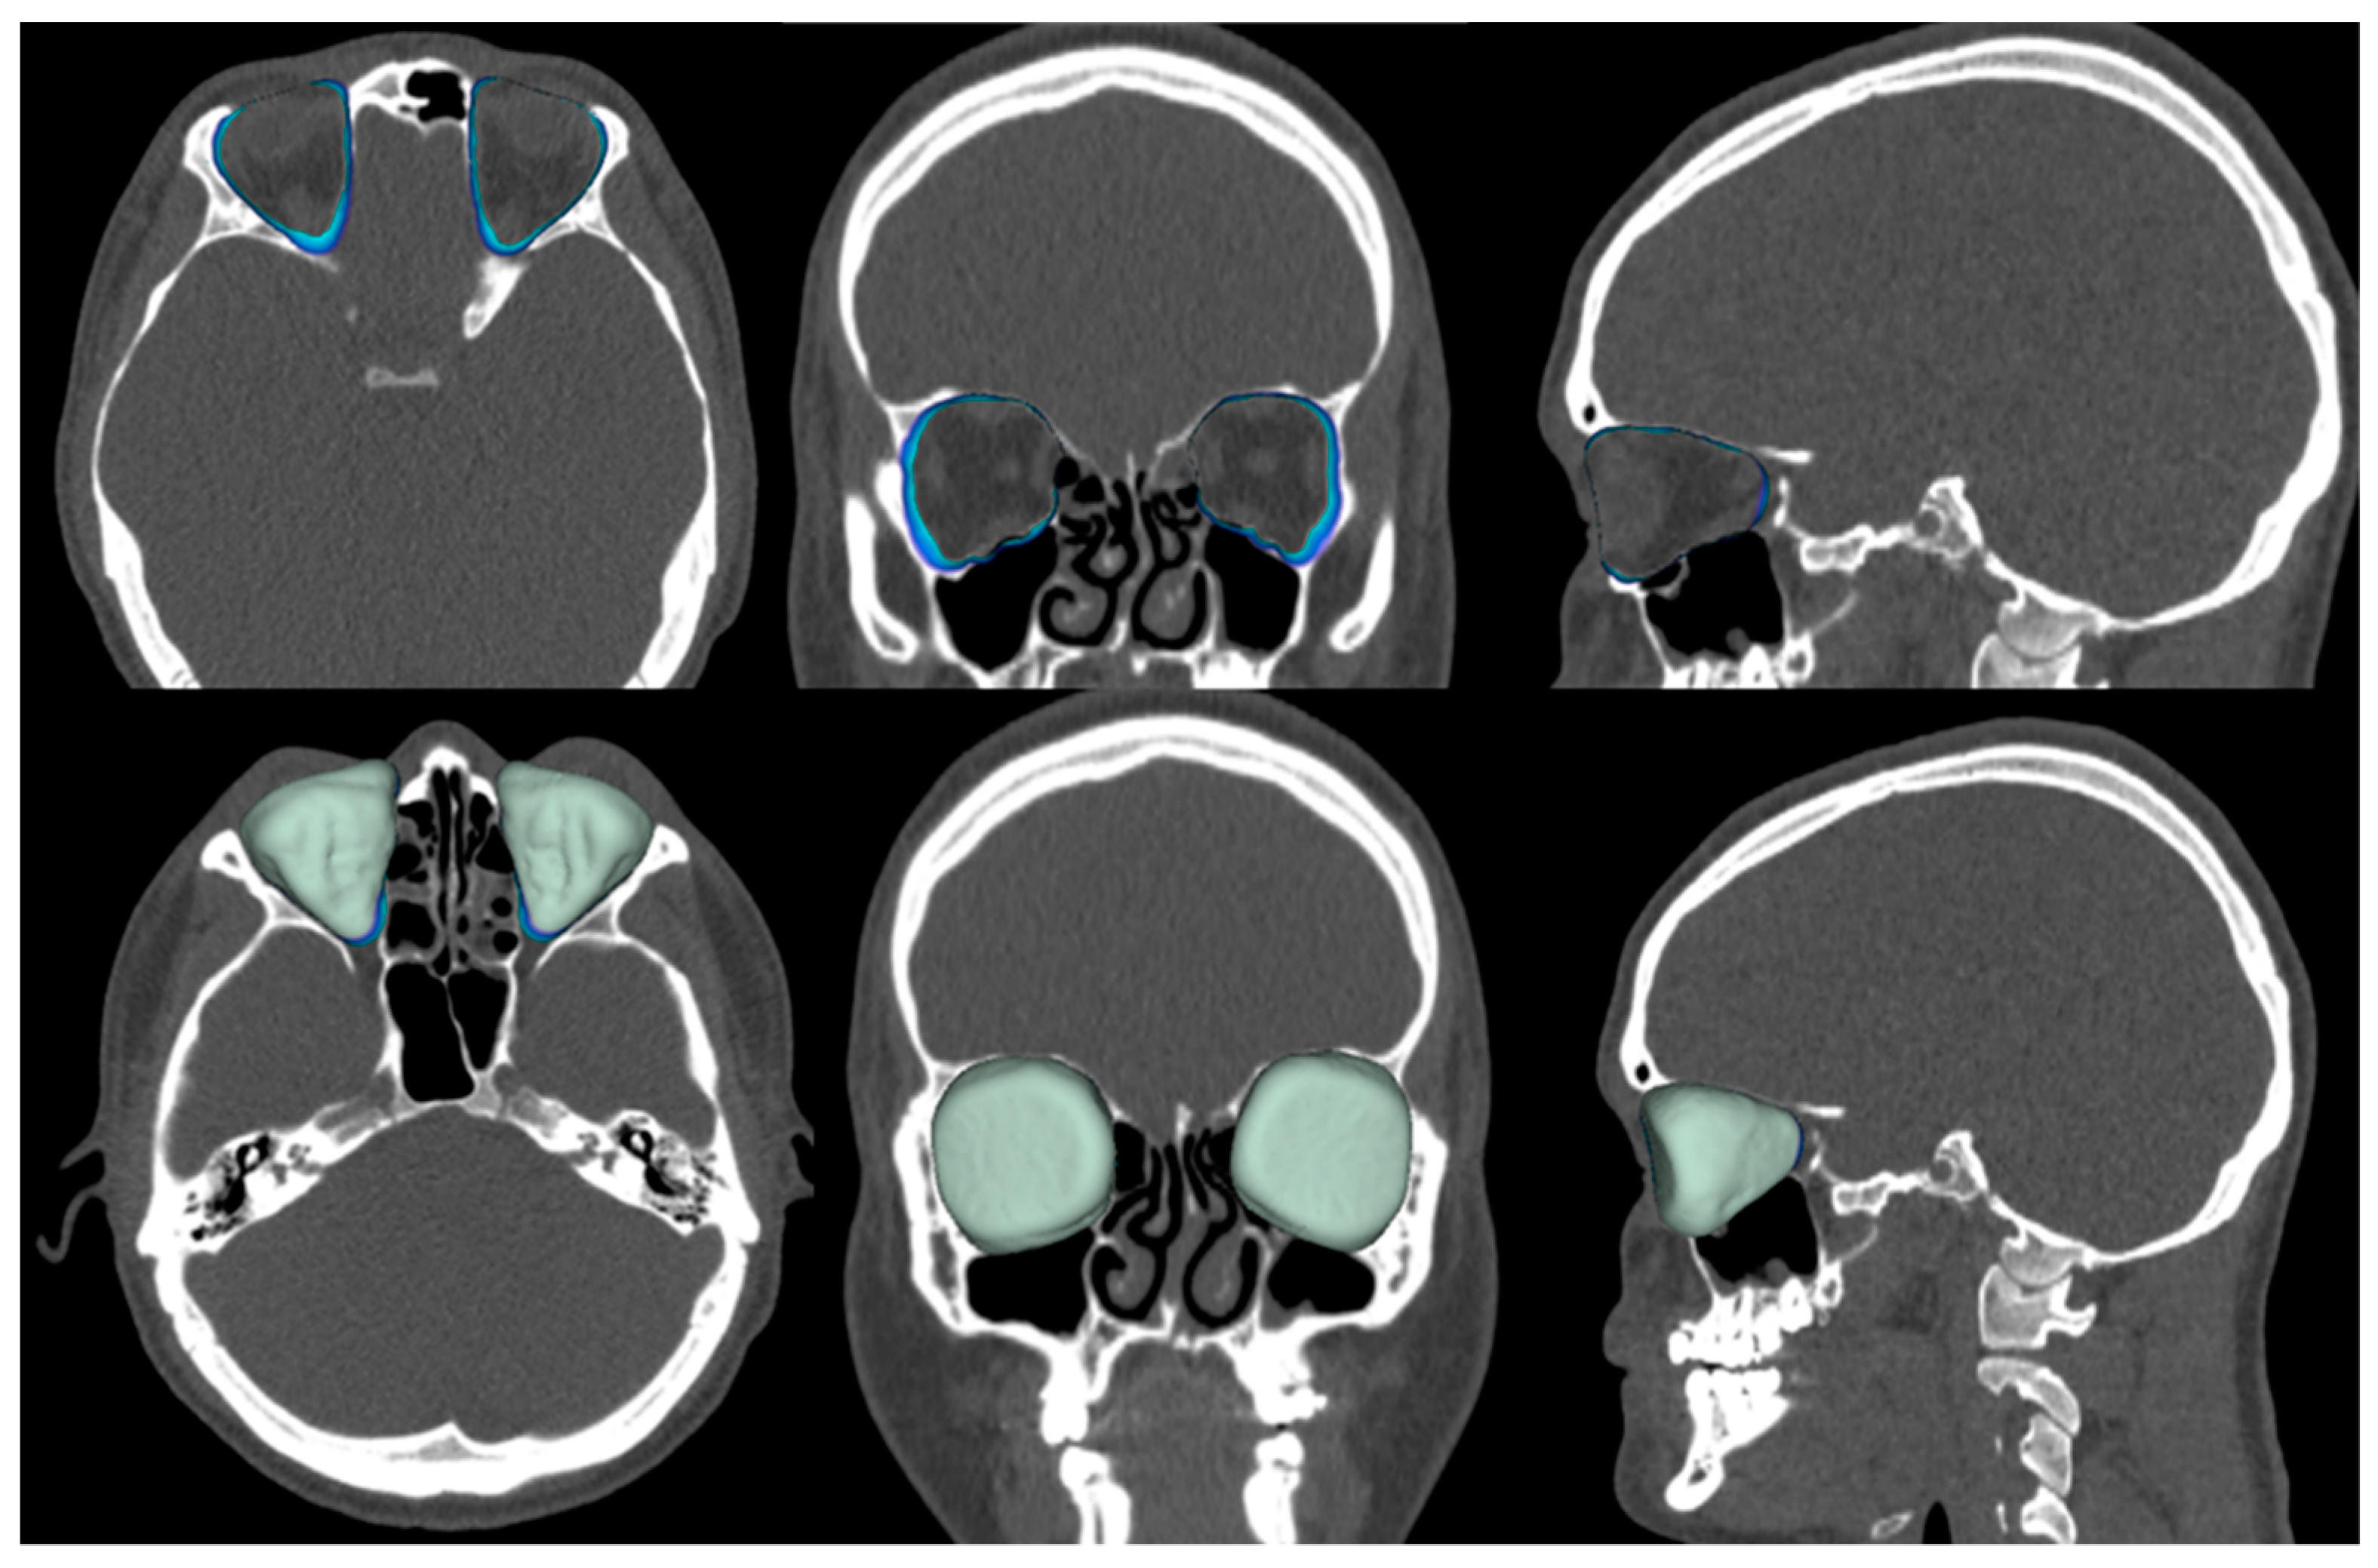

| Cleft Side | Contralat. Side | Mean | 95% CI | 95% CI | DF | p-Value | ||

| Difference | Lower | Upper | ||||||

| Height, cm | ||||||||

| n = 14 | 3.793 | 3.793 | 0 | −0.0751 | 0.0751 | 13 | 1.00 | NS |

| Width, cm | ||||||||

| n = 14 | 3.300 | 3.343 | −0.0429 | −0.0970 | 0.0113 | 13 | 0.111 | NS |

| Depth, cm | ||||||||

| n = 15 | 4.520 | 4.567 | −0.0467 | −0.1326 | 0.0393 | 14 | 0.264 | NS |

| Position, cm | ||||||||

| n = 15 | 6.660 | 6.888 | −0.1733 | −0.3129 | −0.0338 | 14 | 0.019 | * |

| Volume, mm3 | ||||||||

| n = 12 | 25,596.825 | 26,433.167 | −836.3417 | −1464.8051 | −207.8782 | 11 | 0.014 | * |